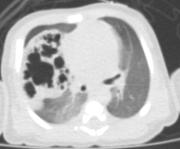

radiotrasparenza, attribuibile a un elemento dell'incubatore. Per una miglior definizione del problema, anche in vista dell'intervento, viene effettuata una TC-polmonare che evidenzia a destra una formazione irregolarmente ovalare di circa 5 cm di diametro massimo, apparentemente ben marginata, con numerose formazioni cistiche aerate circostanti (Figure 2 e Figura 3). Alla luce della diagnosi il bambino viene quindi sottoposto con successo ad intervento di lobectomia parziale dei lobi medio e superiore di destra. |

| Figure

2 a b. TC-polmonare: evidente a dx una formazione

irregolarmente ovalare di circa 5 cm di diametro massimo. | ||